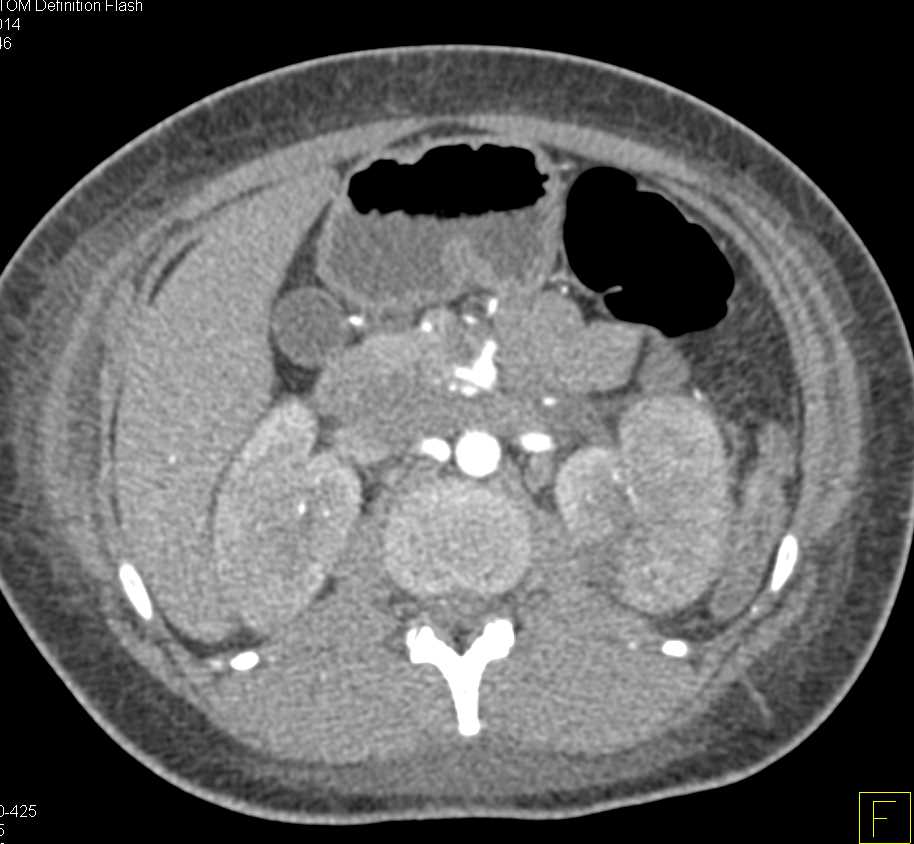

MEST or Mixed Epithelial Stromal Tumor